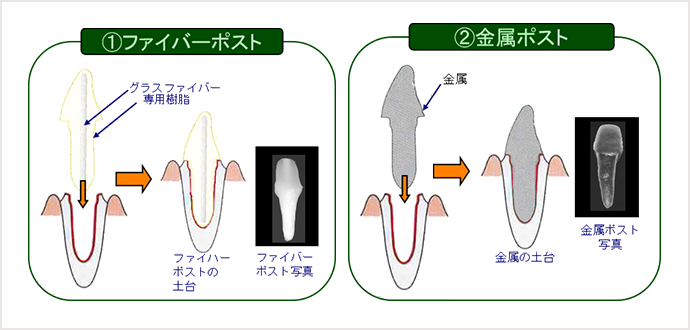

①ファイバーポスト

②金属ポスト

進行した虫歯では、神経や虫歯になった歯を取り除き、土台を入れずにかぶせ物治療をしても、空洞ができ、すぐ外れてしまいます(下図参照)。

そこで歯の土台になる部分(これをポストといいます)を作ります。その材料には①ファイバーポスト、②金属ポストがあります。

特徴 1

金属製のポストは硬すぎる(人の歯の硬さの約6倍)ので、強い力が歯に加わると歯の方が支えきれずに折れてしまうことがあります。しかし歯の硬さとほぼ同じファイバーポストならば歯と一体になってしなるため歯を折れにくくします。また、金属を使用しないので現代病といわれるアレルギーの一つである金属アレルギーの心配もありません。

特徴 2

私たちの歯は、光りを良く通すため、白く明るくしかも自然な透明感もあります。しかし、金属製のポストは全く光を通しませんので、歯肉と歯の境目が暗く不自然になってしまいます。

ところが、ファイバーポストは歯のように光を通すのでとても自然な感じになります。(上写真)さらに金属イオンにより歯肉がやせたり、黒ずむのも防ぐことができます。